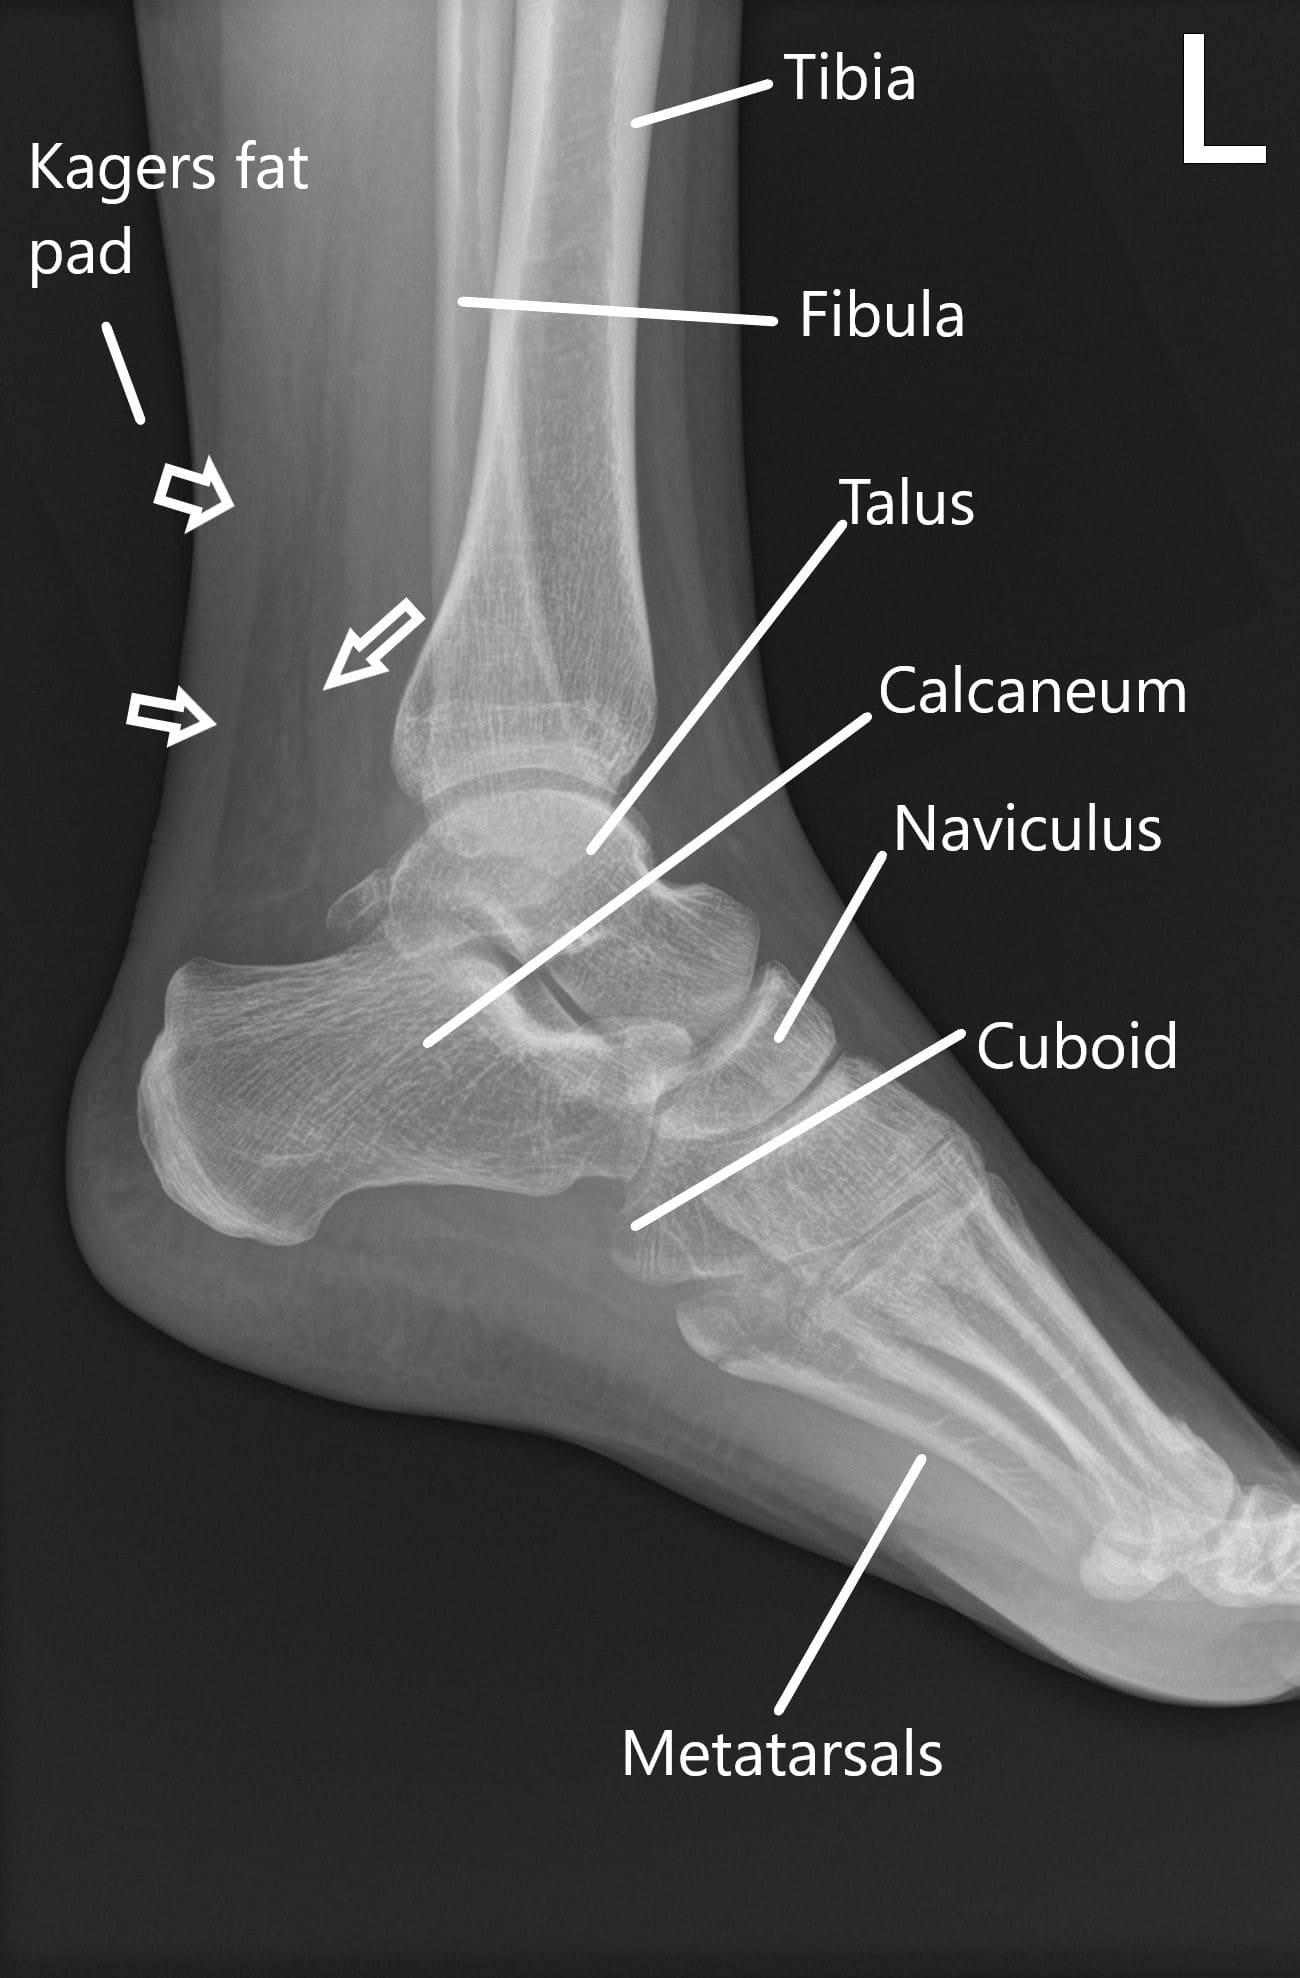

Achilles tendon injuries often cause pain, stiffness, and swelling in the back of your leg near your heel.

We show you only the best treatments for your condition and symptoms—all vetted by our medical team. She will make the correct diagnosis and develop an individualized treatment plan for your specific injury. Warmth around the heel or along the tendon difficulty standing on your toes thickening of the achilles tendon causes of achilles tendinitis